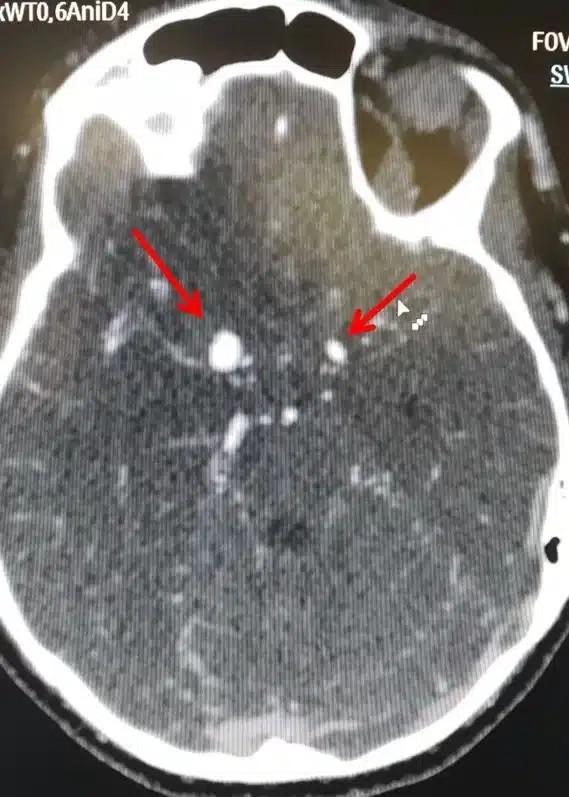

Ένα ανεύρυσμα εγκεφάλου είναι ένα εξόγκωμα ή διόγκωση σε ένα αιμοφόρο αγγείο στον εγκέφαλο.

Το ανεύρυσμα εγεκφάλου μπορεί να παρουσιάσει διαρροή ή ρήξη, προκαλώντας αιμορραγία στον εγκέφαλο (αιμορραγικό εγκεφαλικό επεισόδιο). Πιο συχνά μια ρήξη ανευρύσματος εγκεφάλου εμφανίζεται στο χώρο μεταξύ του εγκεφάλου και των λεπτών ιστών που καλύπτουν τον εγκέφαλο. Αυτό το είδος αιμορραγικού εγκεφαλικού επεισοδίου ονομάζεται “υπαραχνοειδής αιμορραγία”.

Υπάρχουν δύο μορφές εγκεφαλικών ανευρυσμάτων, το σακοειδές και το ατρακτοειδές ανεύρυσμα.

Η συχνότερη μορφή που μπορεί να πάρει ένα ανεύρυσμα είναι η ασκοειδής ή σακοειδής, δηλαδή σχηματίζεται στο αδύνατο σημείο της αρτηρίας ένας σάκος με μίσχο που τον ενώνει με την υπόλοιπη αρτηρία. Φαίνεται σαν ένα μούρο που προβάλλει από μια αρτηρία. Συνήθως αναπτύσσεται σε περιοχές διχασμού αγγείων.

Πιο σπάνια το ανεύρυσμα αρτηρίας του εγκεφάλου μπορεί να πάρει μια στενόμακρη μορφή που περιλαμβάνει όλο το τοίχωμα της αρτηρίας και από τις δύο μεριές (ατρακτοειδής μορφή).